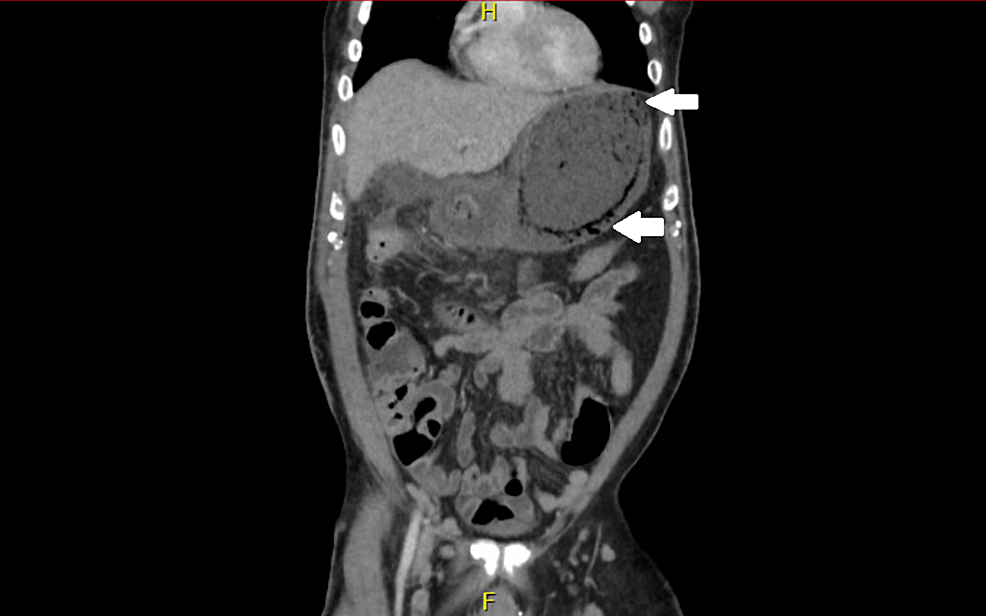

Figure 1 from Emphysematous Gastritis Associated with Invasive Gastric Case Report Of Emphysematous Gastritis Our case was notable in that appropriate and prompt conservative treatments prevented fatal outcome and led to disappearance of hepatic portal venous gas, and this was the. Emphysematous gastritis (eg) is an exceedingly rare cause of severe abdominal pain with an associated mortality reported at greater. 1 as in our case, diabetes mellitus, malnutrition, and renal failure. Recent case literature. Case Report Of Emphysematous Gastritis.

Emphysematous gastritis associated with gastric cancer a rare and Case Report Of Emphysematous Gastritis Recent case literature shows a trend towards conservative management for emphysematous gastritis with several. Emphysematous gastritis (eg) is an exceedingly rare cause of severe abdominal pain with an associated mortality reported at greater. Emphysematous gastritis (eg) is a rare condition characterized by air within the. 1 as in our case, diabetes mellitus, malnutrition, and renal failure. Our case was notable. Case Report Of Emphysematous Gastritis.